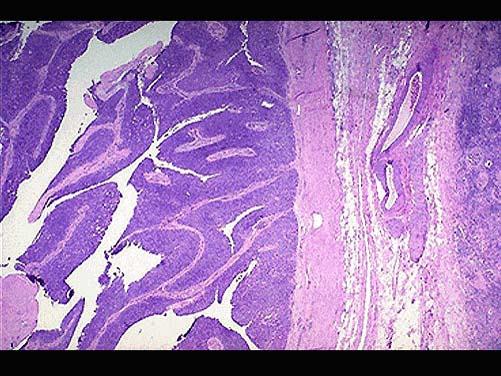

问题 男,65岁。间歇性无痛性肉眼血尿1年。膀胱镜检:膀胱内距输尿管口0.5cm,可见2.5cm×1cm×1cm乳头状肿块,无蒂。静脉肾盂造影可见左肾轻度积水,输尿管全段轻度扩张。行膀胱部分切除后镜检如图所示,下列说法正确的是 ( )

选项 A.该疾病好发部位为膀胱尖部 B.该疾病为膀胱透明细胞癌 C.该疾病手术后不易复发 D.常见的症状为无痛性血尿 E.发生在膀胱的肿瘤大部分为良性

答案 D